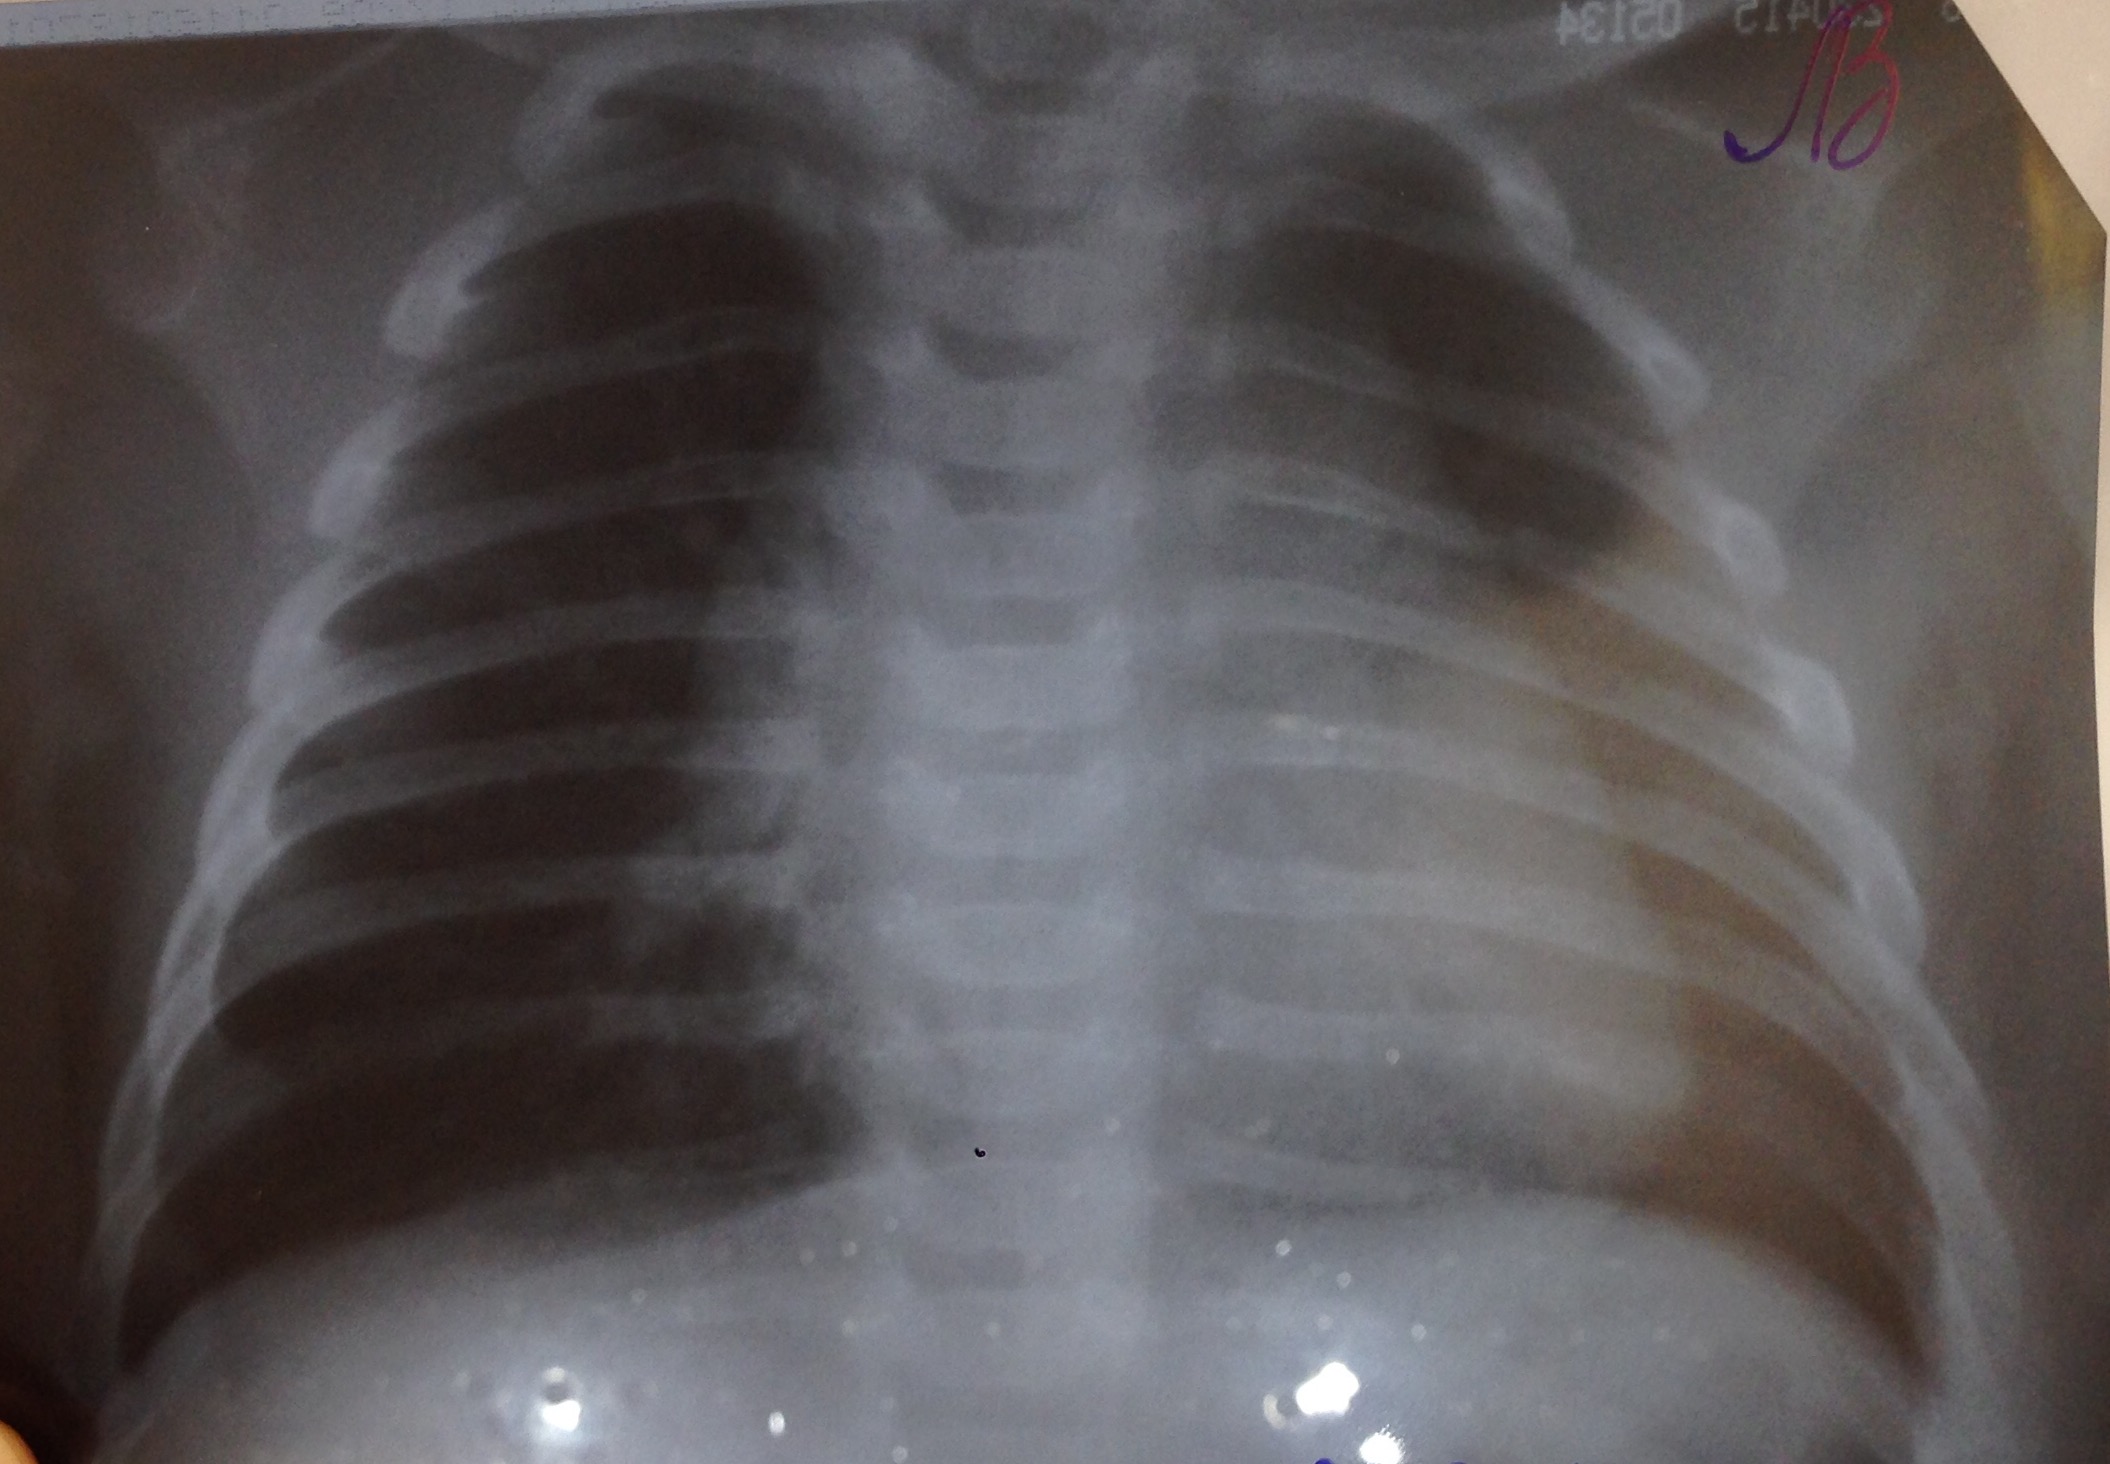

Тимомегалия: что это такое и как проявляется